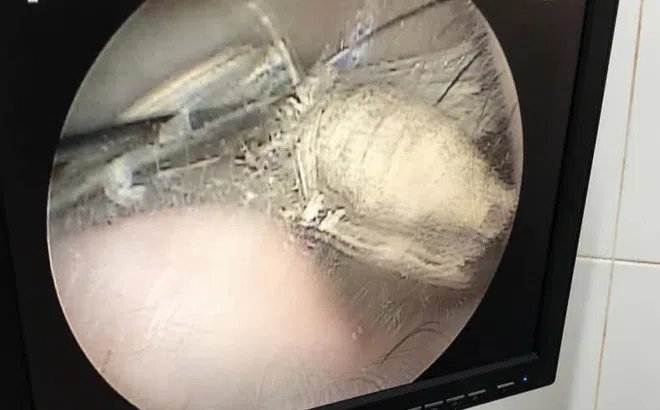

Ù tai, nghe kém do con bọ dài 3cm sống trong tai

Thấy đau tai, ù tai, nghe kém nên người bệnh đi kiểm tra. Tại bệnh viện, các bác sĩ bất ngờ phát hiện ở vị trí ống tai có hình ảnh một con bọ sống trong đó.